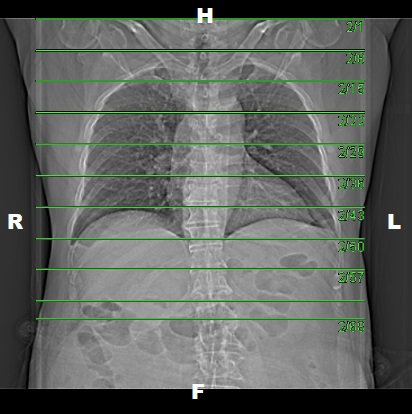

• Plan the Scan FOV (SFOV) box at topogram image

• Set the top line at the level of upper shoulder

• Set the bottom line at the level of iliac crest.

• Ensure the lateral line to cover patient’s body outline.

• Plan the Scan FOV (SFOV) box at topogram image.

• Set the top line at the level upper shoulder.